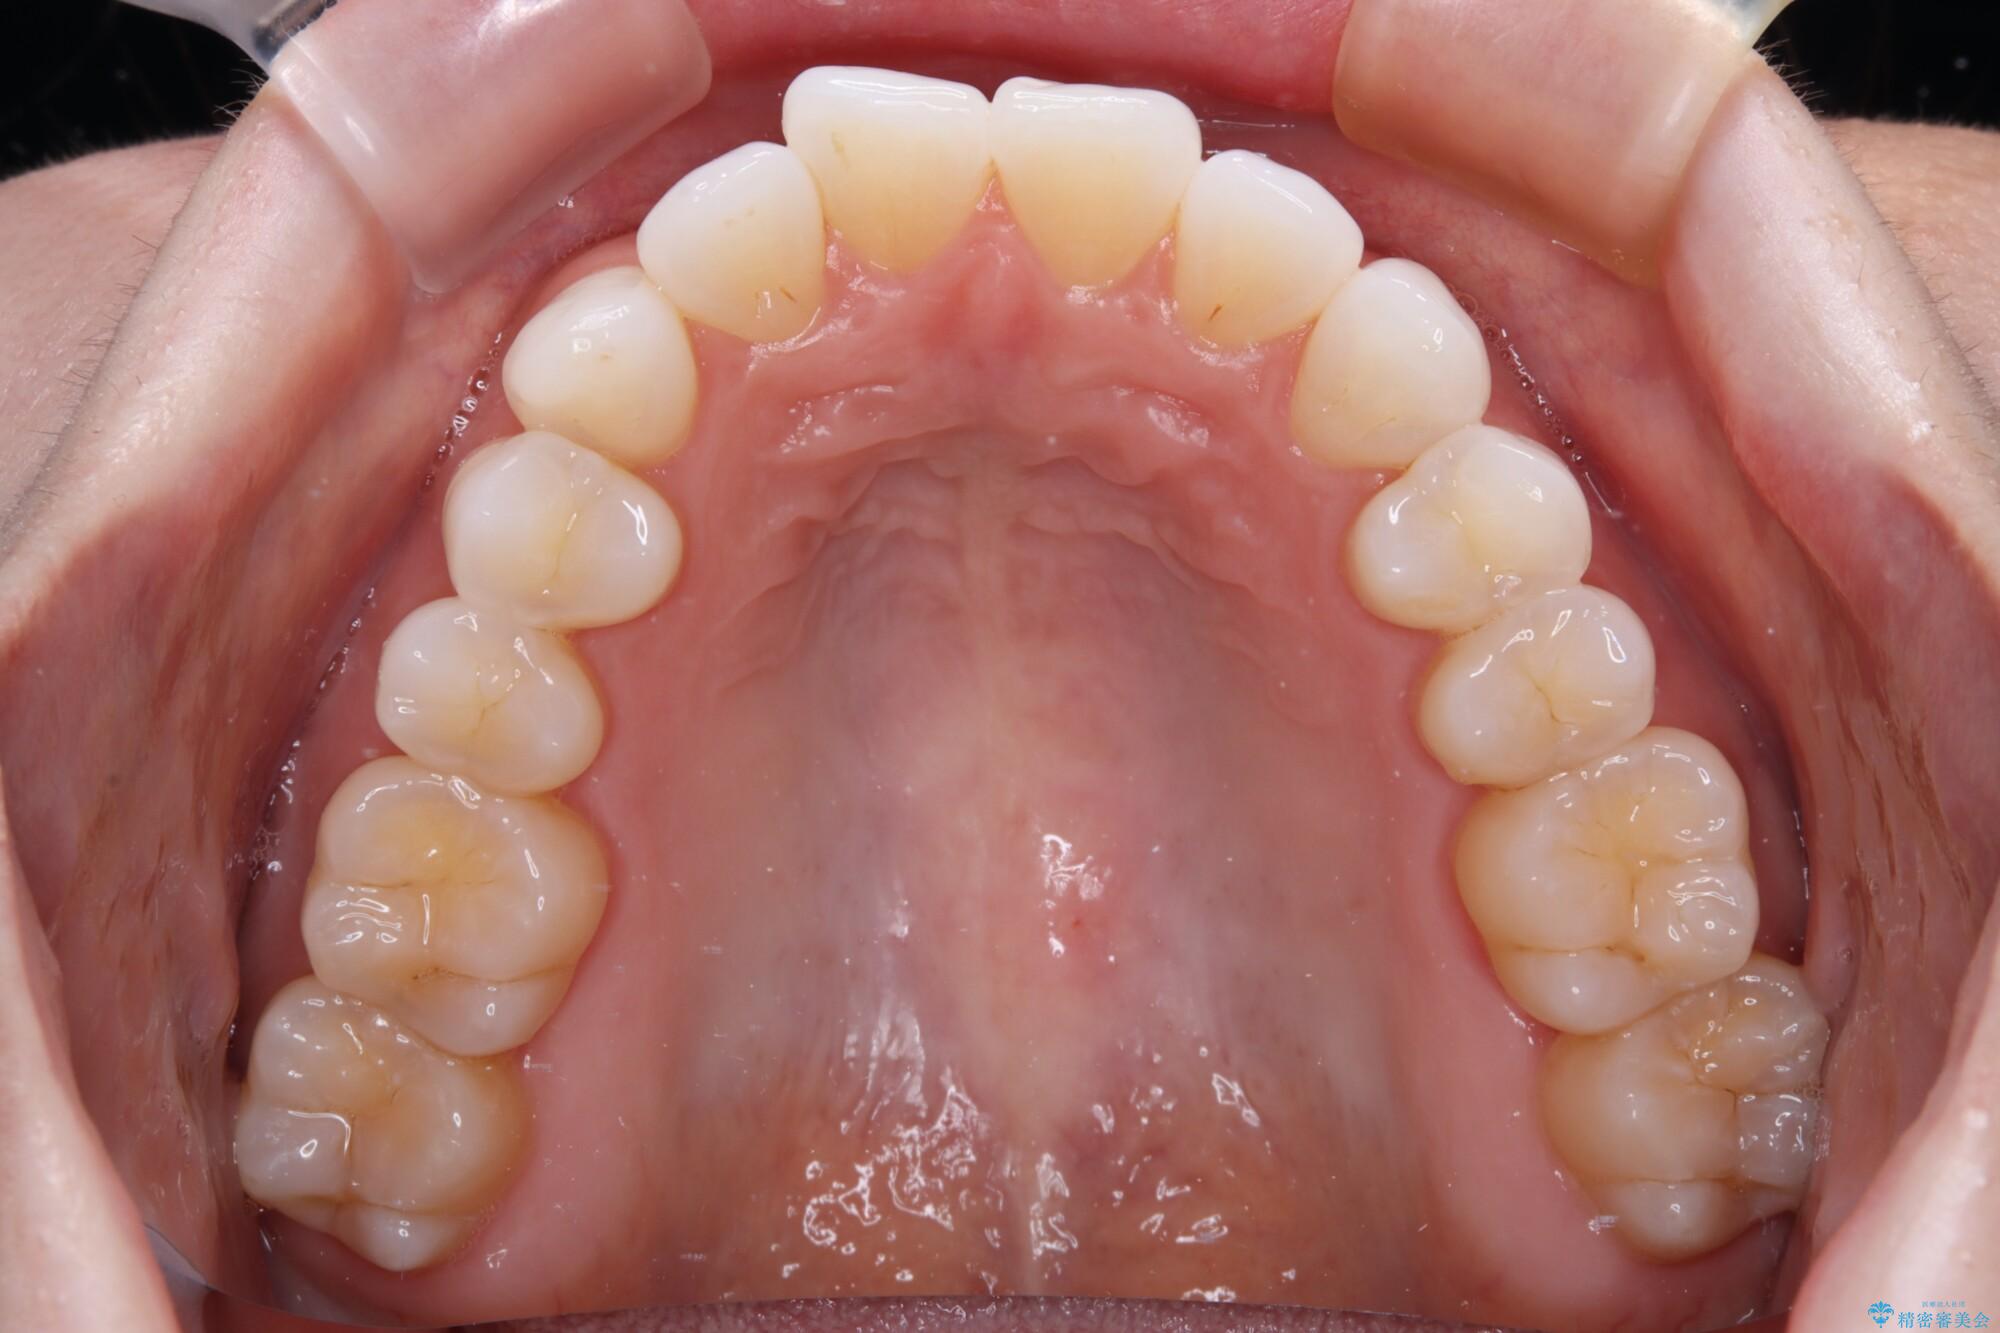

前歯のデコボコをインビザラインで綺麗に

- 上下前歯の叢生を気にして来院された患者様です。

インビザラインでの治療を希望されていて、デコボコの程度が中等度であり、安価なパッケージにて対応可能と判断されたため、インビザライン・モデレートを用いて矯正治療を行うこととしました。

インビザライン・モデレートは、製作できるアライナーの枚数に制限があるため、移動可能な量に限りがあるものの、インビザライン・ライトよりも枚数が多いため、幅広い症例に対応可能です。